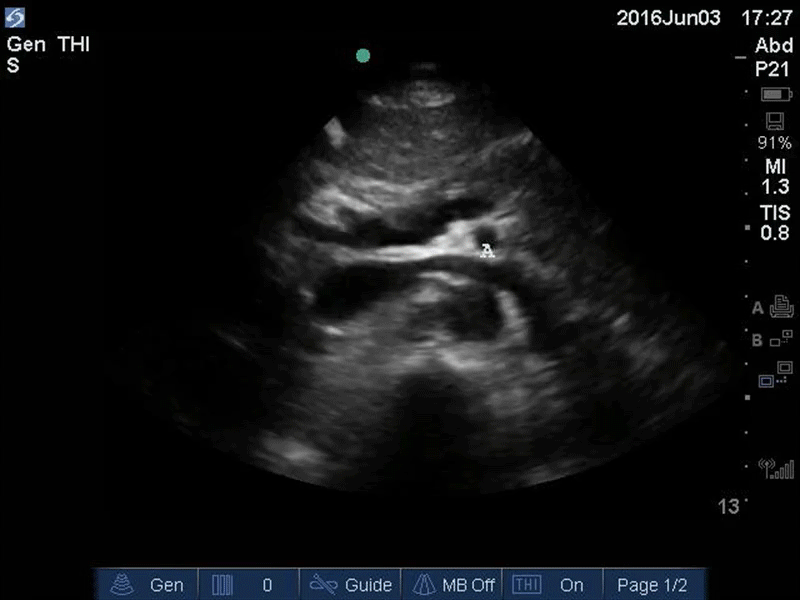

Aorta - Upper Aorta - Colorized - The POCUS Atlas

Orange: Yellow: Liver, Light blue: Pancreas, Aqua: splenic vein/portal confluence, Blue: IVC with left renal vein, Purple: SMA, Red: Aorta, Orange: Spine Images: Dr. Lindsay Davis, Dr. Hannah Kopinski. Image Editing: Michael Amador and Dr. Matthew Riscinti